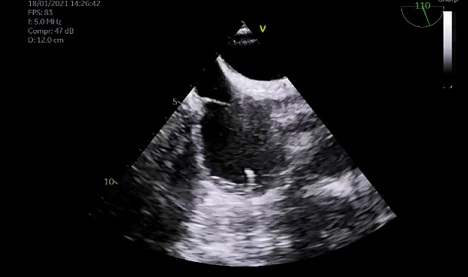

A TTE demonstrated a normal ejection fraction with mild aortic stenosis and regurgitation and no evidence of valvular or lead vegetation. A TEE did not reveal signs of cardiac infection either (Figure 1).

Figure 1: Tranesophageal Echocardiogram. Transesophageal echocardiogram did not reveal any vegetation on valves or pacer’s leads.